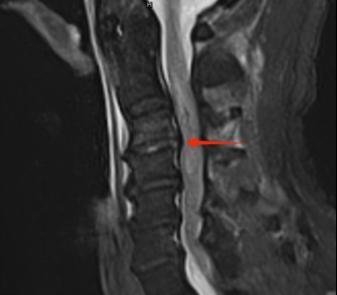

近日,我院收治一名高龄男性患者,诊断为“颈4椎骨折、颈脊髓损伤伴完全四肢瘫”,合并肺部感染与深静脉血栓,胸骨柄平面以下感觉活动消失,生活完全依赖,且面临呼吸衰竭、压损等高危风险,护理挑战极大。

1.2  患者术前影像